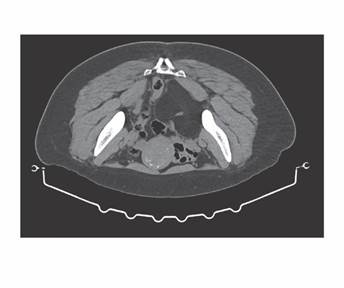

En RM pelviana de octubre del 2022 se apreció imagen ocupacional de aproximadamente 9,5 x 10 cm en hemipelvis derecha con alta intensidad de señal en secuencias potenciadas en T1 y T2 sugiriendo tumoración de estirpe grasa con efecto masa sobre estructuras intraabdominales, desplazando el recto, cuello uterino y vagina hacia el lado izquierdo (Figura 2 y Figura 3). En su porción lateral se introducía ampliamente por escotadura ciática derecha. Se procedió a la realización de punción aspiración con aguja fina, con abordaje posterior, bajo control de tomografía axial computarizada (PAAF-TAC) (Figura 4) de masa intrapélvica, obteniendo muestra para estudio histológico. El informe anatomopatológico confirmó tejido de aspecto adiposo maduro, compatible con lipoma por lo que se derivó a consulta de Cirugía.

Figura 4. Imagen de TAC abdominal para guiar punción PAAF, previa intervención.